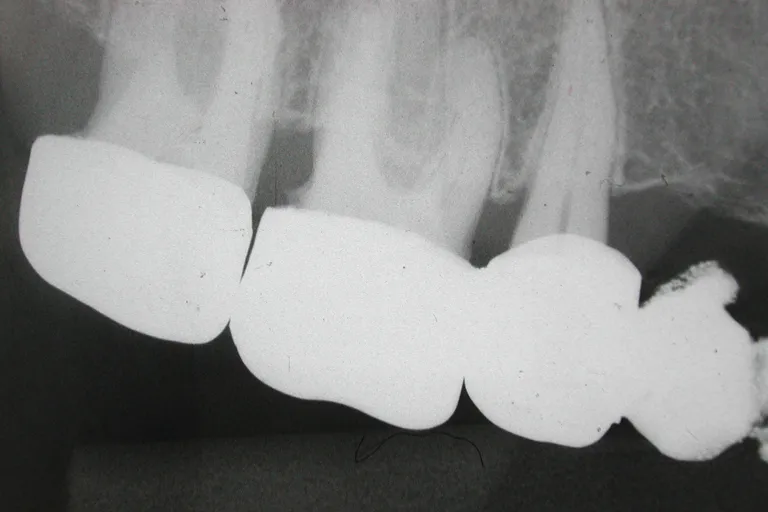

■術前・他医院で治療された被せもので精度が低く歯との境の縁があっていないため段差ができています

■術 前■

被せ物の縁が

あっていない

■術前・被せものはセメントを盛って取付け段差を埋めますが縁の制度が低いと境目のセメントが取れた時に大きな段差ができます

■保険対応の被せ物

保険で指定された金パラジウム合金(主成分は50%近くは銀)を使います。目で見ながらの作業で、縁の合わせ方は、良くて100ミクロン(10分の1ミリ)です。セメントして付けると、150ミクロンくらい縁が合っていません。この程度の精度では、短期間では問題ありませんが、虫歯にかかりやすい人では、縁からセメントが溶けて、2次的な虫歯が発生することが多く起こります。

レントゲンで、縁が歯と合っていない被せ物では、このレベルの何倍も不適合であることは珍しくありません。被せものの縁に爪が引っかかるレベルでは、歯の寿命に影響がある場合も出てきます。当クリニックでは、自費において、さらにレベルの高い治療ができており、保険の対応においても、十分な配慮が行われています。当クリニックの被せ物は保険であっても、爪が引っかかる、レントゲンでズレがあるということはありません。